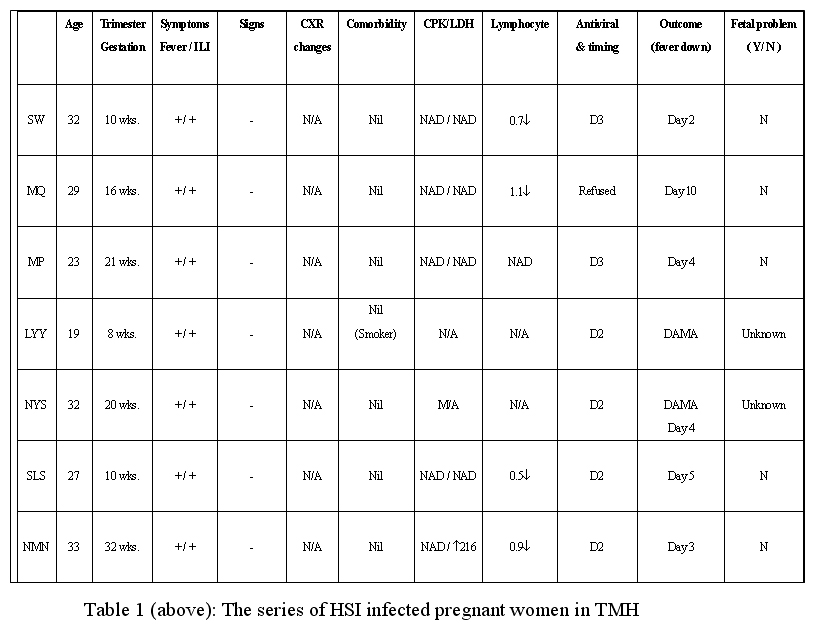

On arrival, her blood pressure was 115/85mmHg and her pulse was 110/min. She had fever with temperature 38.2oC. Her body mass index was 30 kg/m2. Her respiratory rate was 20/min with SaO2 95% on 3L/min oxygen administered via nasal cannula. Bilateral basal crepitations were heard during physical examination. Her JVP was not elevated and cardiovascular examination showed normal heart sounds with no murmurs. Abdominal examination was unremarkable. CXR showed bronchopneumonic changes over bilateral lower zones.

She was started on oral Tamiflu 150mg twice daily, oral linezolid 600mg twice daily and oral levofloxacin 750mg daily on admission. She developed desaturation and was admitted to the intensive care unit (ICU) for close monitoring on the same day of admission. She deteriorated further and was intubated on 18 July 2009. She was given low dose inotropic support with noradrenaline. Relenza nebulization, simvastatin and IVIG were also prescribed to her during her stay in ICU.

She responded to the treatment with gradual improvement and was extubated on 24 July 2009. She was transferred to the general medical ward for further treatment on 16 July 2009. Oxygen supplement was gradually weaned off. She was discharged home on 30 July 2009.